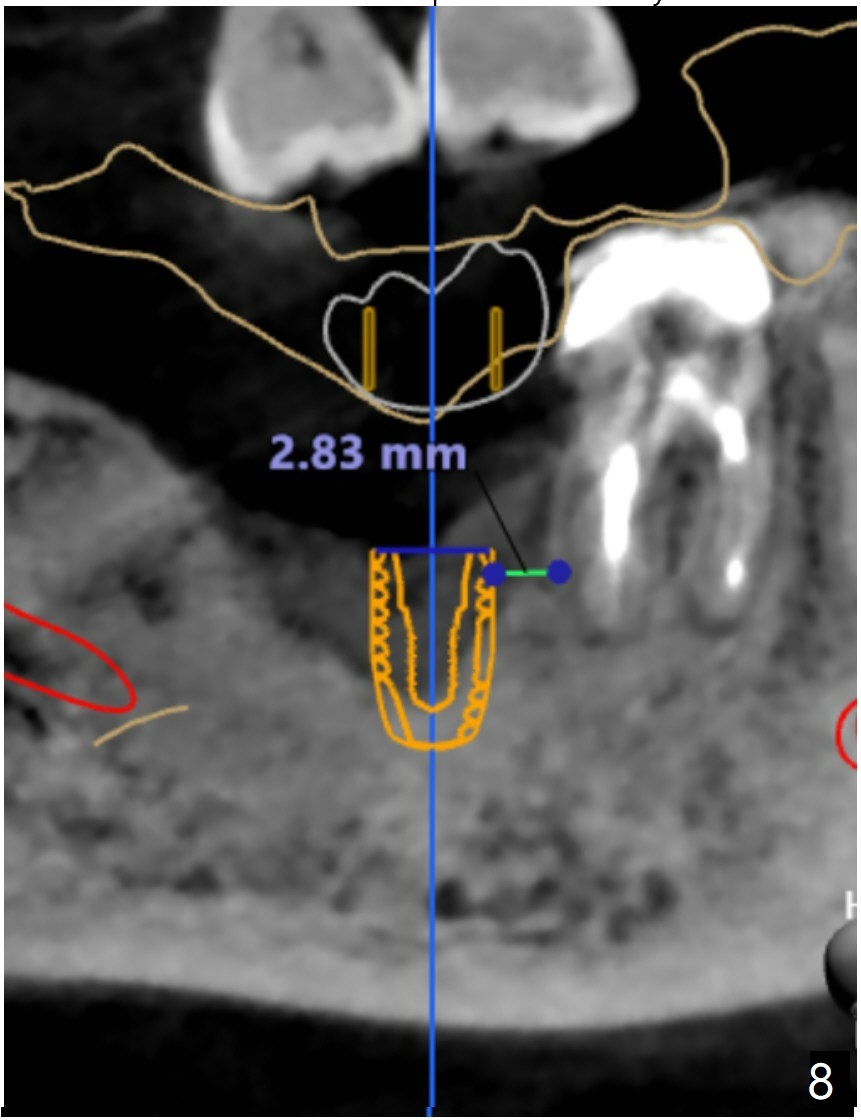

And let's not tap it for the grafted area. I see the same bone density but the different contrasts on the CT data. So I will make sure to include that on the sequence next time. For the distalized position, I don't think it is distalized that much because it is good to have at least 2-3mm distance between implant to the nature root. I've measure it and it was 2.83mm in between (Fig.8). But we can make this space narrower if you want.